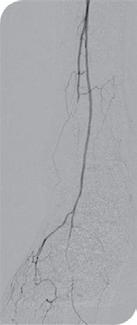

Researchers have shown that quiescentinflow single-shot (QISS) magnetic resonance imaging (MRI) is able to identify more below-the-knee vessel segments than digital subtraction angiography (DSA) in patients with chronic limb-threatening ischaemia (CLTI). Taking first prize for best abstract, Alexander Crichton (Houston, USA and Birmingham, UK) shared this and other findings at the 39th European Society for Vascular Surgery (ESVS) annual meeting (23–26 September, Istanbul, Türkiye).